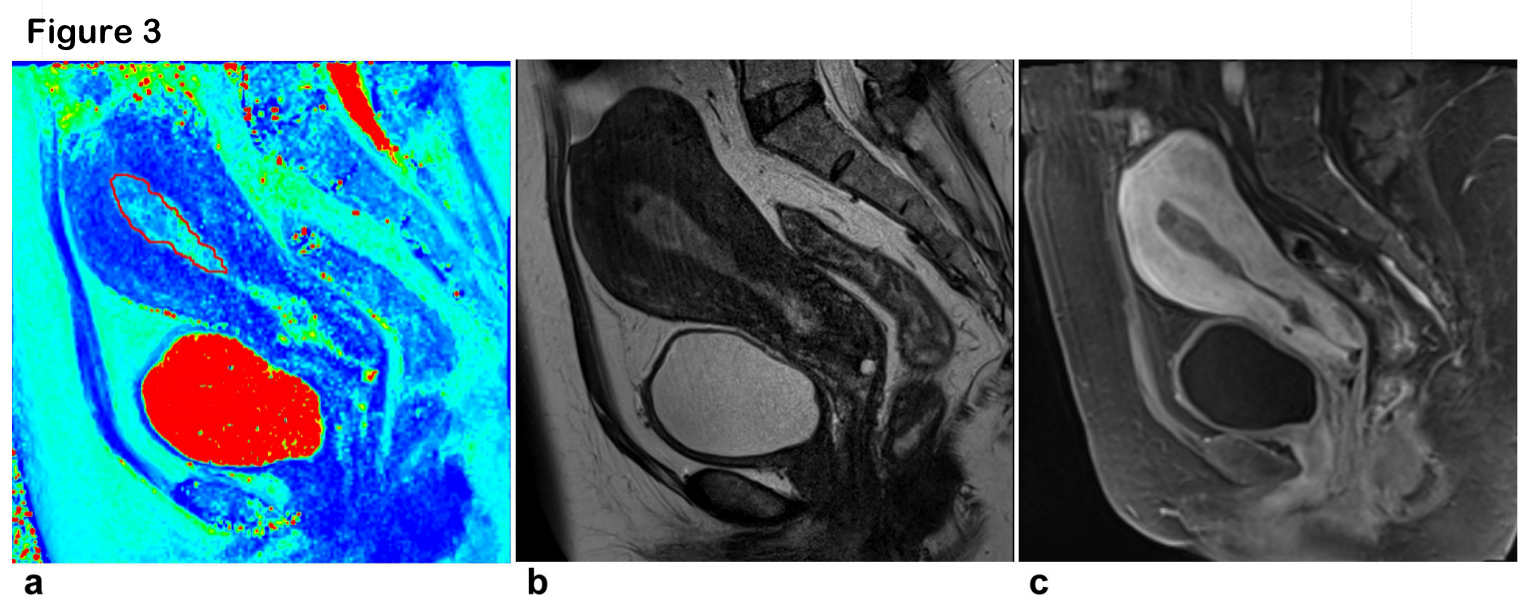

Figure 3 The region of interest were manually placed in the lesions according to lesion morphology and size. (a) Sagittal T2 map, (b) Saggital T2-weighted image and (c) Saggital enhanced image show a endometrial cancer in a 52-year-old woman.